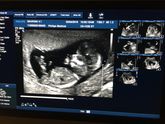

2 апреля 2018 11:07 Сегодня наш первый скрининг ??? сказали что все хорошо и со стопроцентной уверенностью, будет мальчик ) делала на волоха в жк, у врача Петровой Татьяны Александровной , прекрасный врач , все показала и рассказала , дали посмотреть и сфотографировать … Читать далее